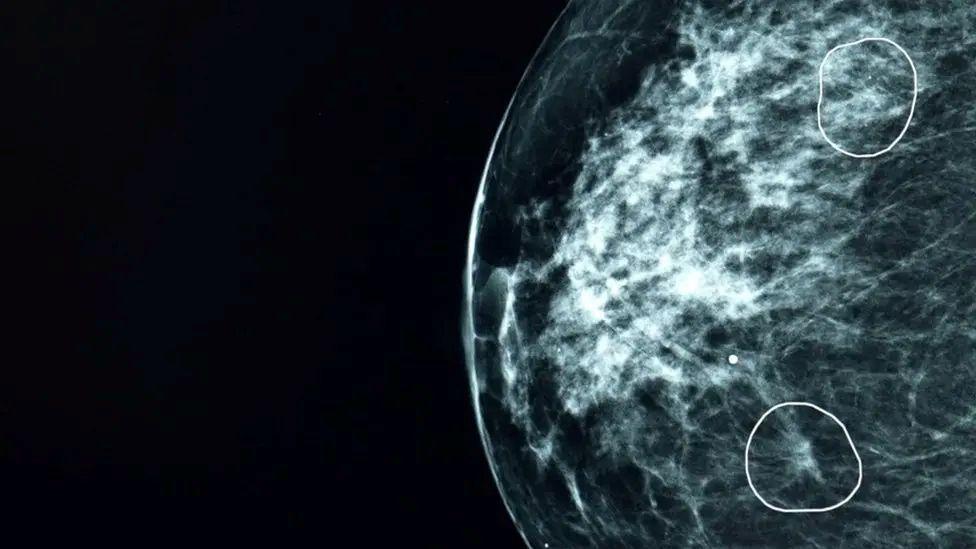

Es capaz de identificar áreas pequeñas y difíciles de ver en las mamografías que podrían no ser percibidas por el ojo humano.

El estudio sobre la detección de cáncer de mama, publicado en la revista Nature Cancer, indicó que podría incrementar la detección en un 10.4%.

“Cuando llegué a la cita, me dijeron que era la IA la que había detectado algo”.

“Me hicieron una tomografía y el médico especialista confirmó que el diagnóstico de la IA era correcto: había un pequeño tumor de grado 2, demasiado pequeño para ser detectado a simple vista”.